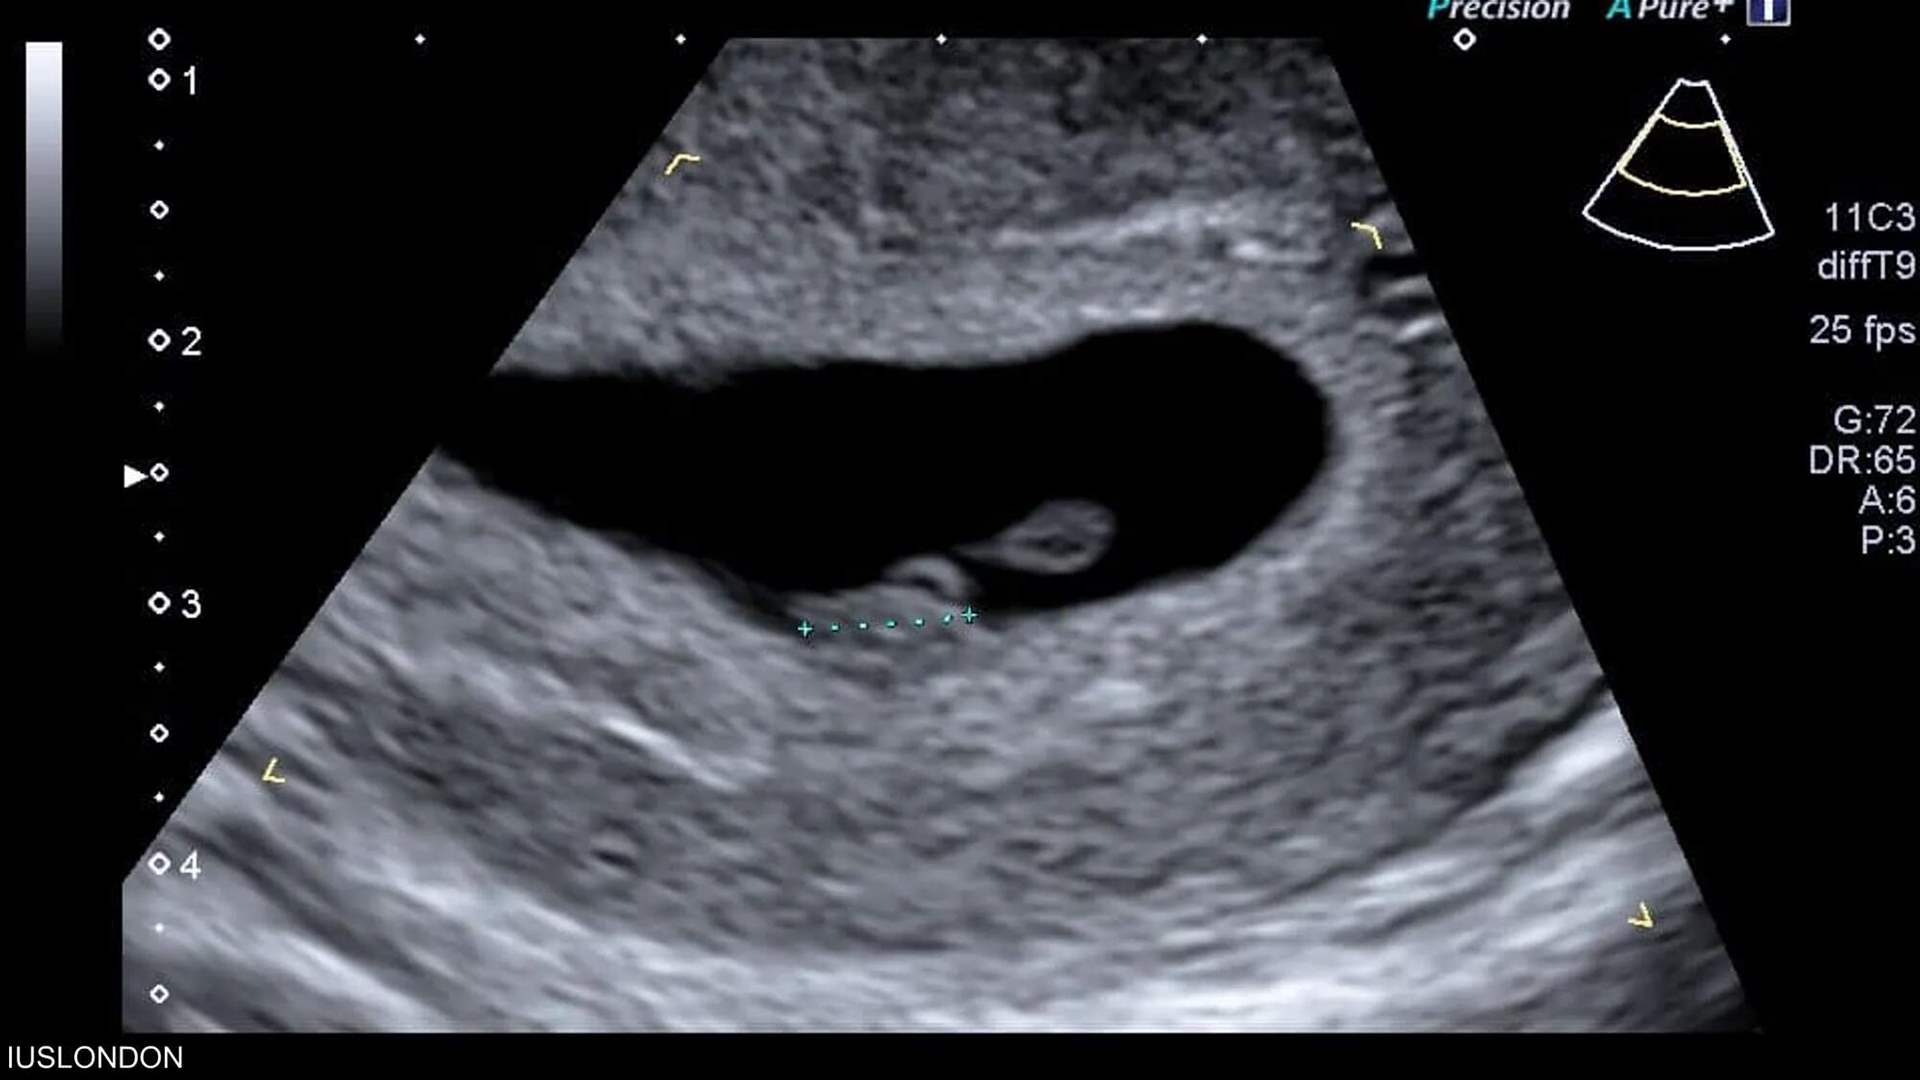

كشفت دراسة حديثة أن الذكاء الاصطناعي قد يصبح أداة ثورية في تحديد الموعد الدقيق لولادة الأطفال، بنسبة دقة تصل إلى 95%.

لكن مجموعة من الباحثين الأميركيين تقول إن استخدام الذكاء الاصطناعي لتحليل صور الموجات فوق الصوتية يمكن أن يتنبأ بموعد ميلاد الطفل بدقة تصل إلى 95%

وباستخدام برنامج تم تطويره وتدريبه باستخدام أكثر من مليوني صورة بالموجات فوق الصوتية لنساء أنجبن أطفالهن بين عامي 2017 و2020، قام العلماء بقياس مدى قدرة الذكاء الاصطناعي على تقدير ما إذا كان الطفل سيرى النور في موعد ولادته أم لا.